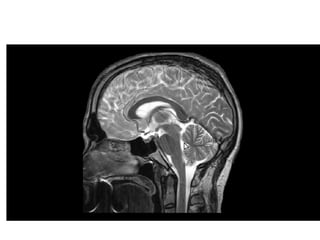

Anatomical positioning of ventricles of brain

• Two lateral ventricles

• “C” shaped

• Capacity- 7to10 ml

• Communicates with 3rd

ventricle through

foramen of Monro.

• Lined by ependyma

Ventricular System